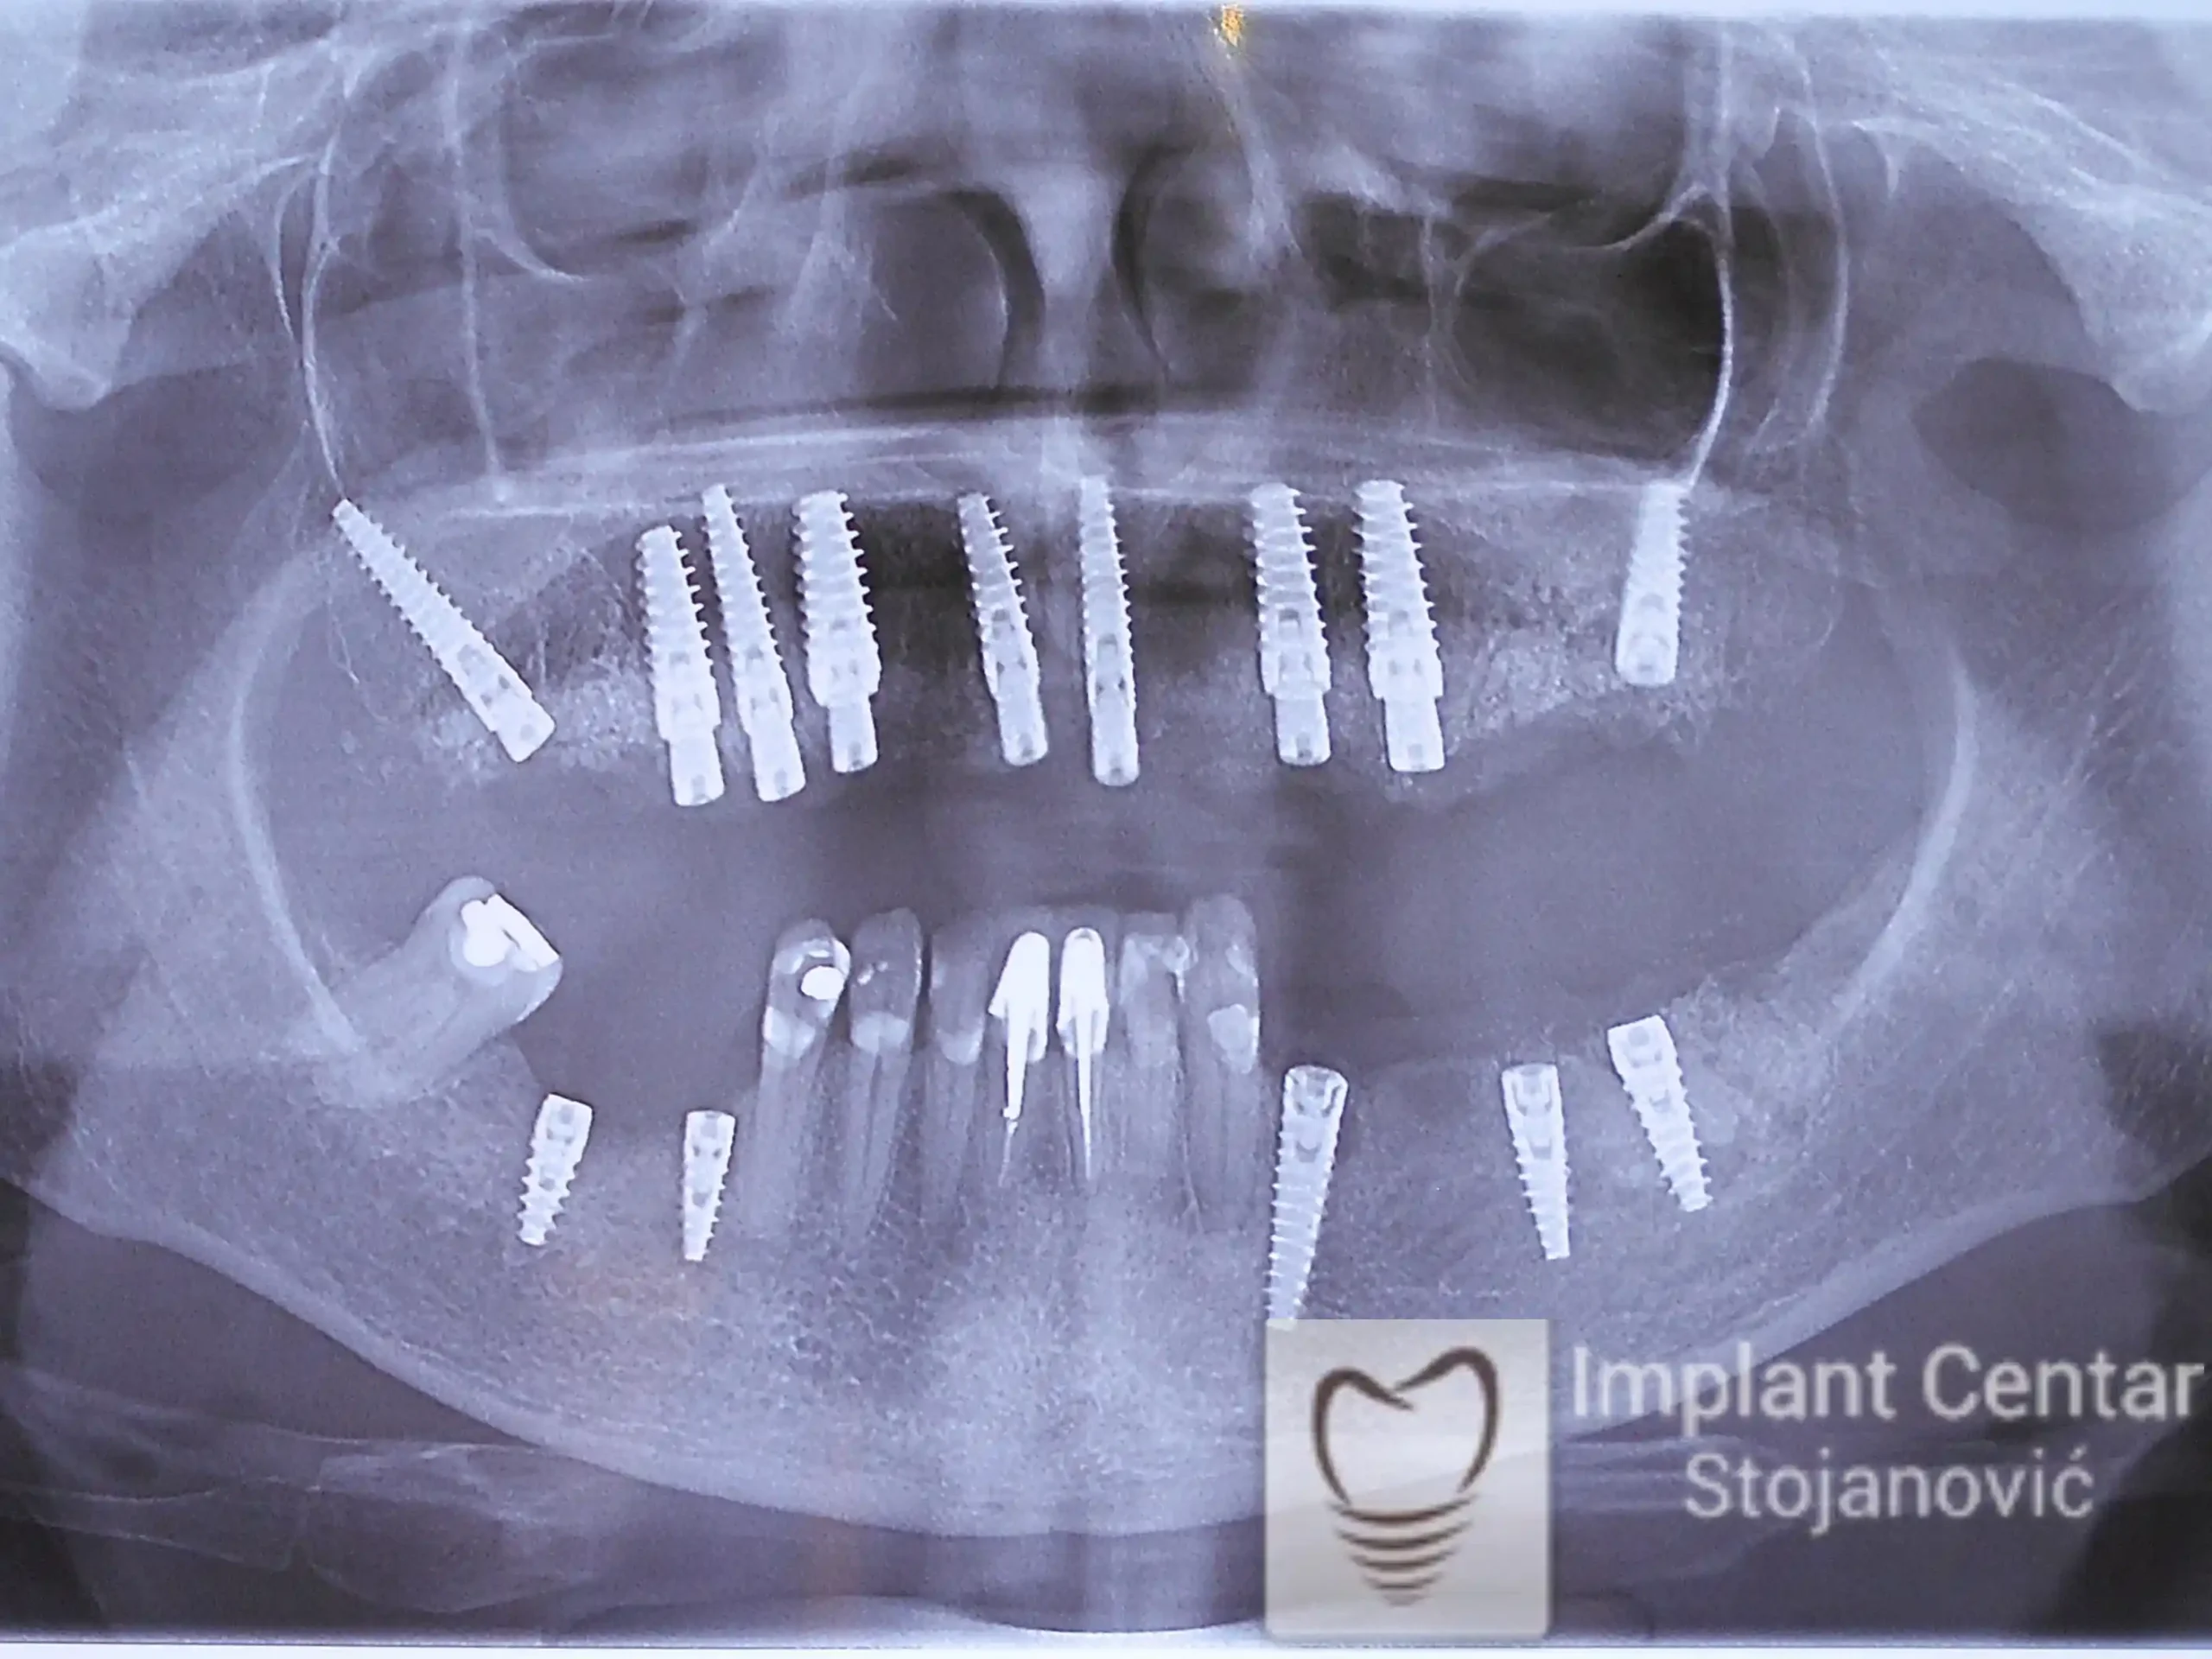

Nakon detaljnog kliničkog pregleda i analize radioloških snimaka, izrađen je sveobuhvatan plan terapije sa ciljem uklanjanja mobilnih proteza i postizanja maksimalne funkcionalne i estetske rehabilitacije. Zbog loše biološke vrednosti preostalih zuba, doneta je odluka o njihovom vađenju i ugradnji dentalnih implantata.

Poseban terapijski izazov predstavljalo je premošćavanje defekta nastalog usled rascepa, kao i ograničena količina raspoložive kosti u gornjoj vilici. Primenom većeg broja implantata i odgovarajućih procedura nadoknade kosti, postignuta je stabilna osnova za fiksni protetski rad.

Tokom perioda oseointegracije, pacijent je bio zbrinut fiksnim privremenim krunicama, čime je već pet dana nakon intervencije obezbeđena potpuna funkcionalna i estetska rehabilitacija. Nakon završetka perioda integracije implantata, izrađeni su definitivni cirkonijum-keramički mostovi na implantatima.